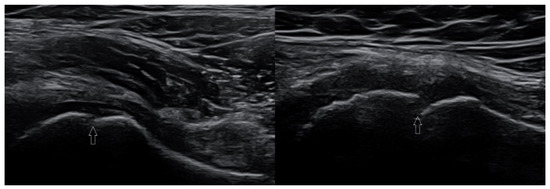

We present basic differences in the musculoskeletal ultrasound examinations between adults and children. Examiners who deal with adults on a daily basis have shared concerns about examining children. Such concerns may arise from the different approach to child ultrasounds, but they also come [...] Read more.

We present basic differences in the musculoskeletal ultrasound examinations between adults and children. Examiners who deal with adults on a daily basis have shared concerns about examining children. Such concerns may arise from the different approach to child ultrasounds, but they also come from differences in anatomical characteristics according to developmental age. We discuss the presence of growth plates, as well as non-mineralized parts of the bones. We also refer to the pathologies most often found in ultrasounds in early developmental stages. In the PubMed database, the set of keywords: “msk ultrasound in children”, “pediatric msk sonoanatomy”, “coxitis fugax”, “pediatric Baker’s cyst”, “Baker’s cyst ultrasonography”, “bone septic necrosis in ultrasonography”, “ultrasonography in juvenile idiopathic arthritis”, and “ultrasonography in juvenile spondyloarthropathies”, was used to identify a total of 1657 results, from which 54 was selected to be included in the article. We discuss the problem of osteochondritis dissecans, Osgood-Schlatter disease, examples of ligament injuries (especially in relation to the knee and ankle joints), exfoliation of growth cartilages, osteochondroma, exudates and inflammations affecting joints, and Baker’s cysts. In this way, we have collected useful information about the most common diseases of the musculoskeletal system in children. Full article